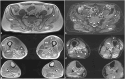

Recessively inherited limb-girdle muscular dystrophy type 1, caused by mutations in the calpain 3 gene, is the most common limb-girdle muscular dystrophy worldwide. Recently, cases of autosomal dominant calpainopathy have been described. A man was referred to our neurological outpatient clinic at the age of 54 for persistent hyperCKemia (>1000 U/l) associated with muscle fatigue and myalgia. Clinical examination revealed mild proximal weakness in the lower limbs. His brother exhibited a moderate increase in serum creatine kinase levels (up to 2000 U/l) without other signs of myopathy. Their father experienced slowly progressive lower limb weakness after the age of 50. The calpain 3 variant c.1478G>A (p.Arg493Gln) in the heterozygous state was identified in both brothers. In silico modeling studies predict that this substitution may disrupt protein folding. This represents the first description of the heterozygous p.Arg493Gln calpain 3 variant as a potential cause of mild calpainopathy.